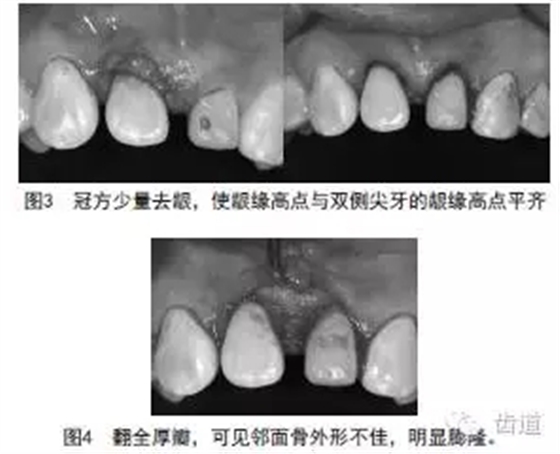

①向患者交代手術(shù)方案及風險,簽知情同意書;患者目前處于皰疹感染期,建議擇期手術(shù),患者因工作忙,堅持今日手術(shù)。②常規(guī)消毒鋪巾。③12和22在復方鹽酸阿替卡因(含腎上腺素)局部麻醉下(STA無痛麻醉)下,冠向距齦緣約1~2mm內(nèi)斜切口,齦緣高點與13和33平齊(圖3),溝內(nèi)切口,翻黏骨膜全厚瓣,暴露牙槽嵴頂,可見12和22牙間隙處牙槽嵴頂略凸(圖4),與齦緣約2~3mm,12和22唇側(cè)近中渦輪去骨約0.5~1mm,骨成形,未降低骨高度(圖5),牙齦修整,牙間乳頭處5/0不可吸收線間斷縫合3針(圖6),上牙周保護劑。④醫(yī)囑:0.12%復方氯己定溶液漱口,每日2次,1周;口服抗生素3天,積極控制皰疹感染。⑤1周后拆線。